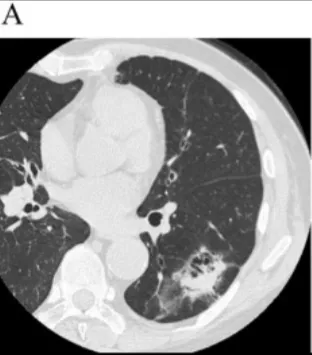

非常有趣的肺ct莲蓬征你见过吗